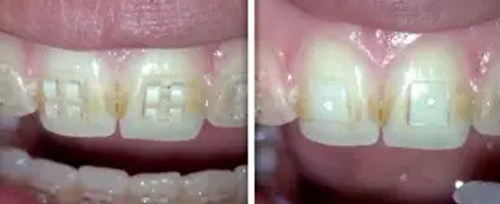

Orthodontic bracket removal